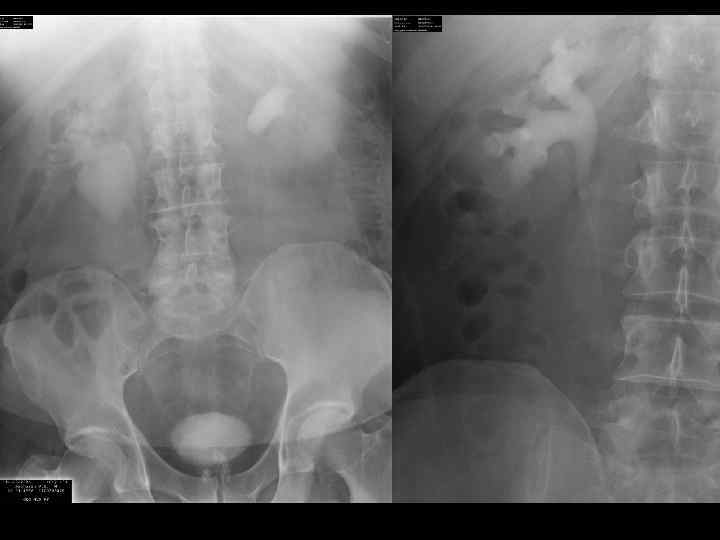

Больной К.

Больной А.

ротация

С-r